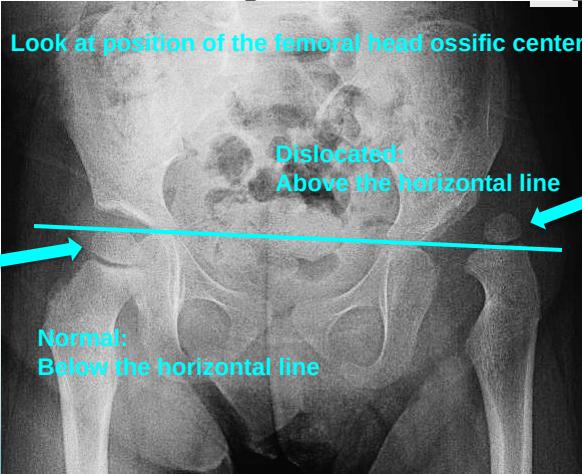

1. Horizontal Line Through Tri-radiate Cartilage

- Normal: Femoral head ossific center below the horizontal line

- Dislocated: Femoral head ossific center above the horizontal line